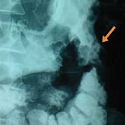

Gastrocolic fistula secondary to primary gastric lymphoma

Toufik Berri

PAMJ. 2014; 17: 15. Published 15 January 2014